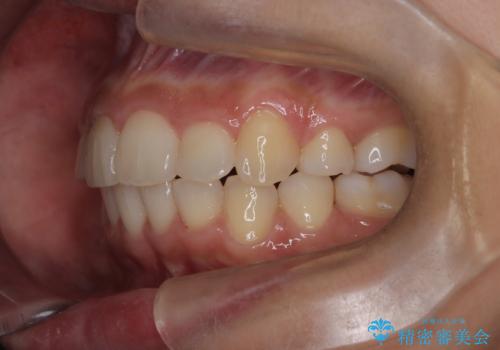

- 前歯の凸凹を主訴に来院されました。

抜歯を行い、ワイヤー矯正にて治療を行いました。

凸凹もなくなり、歯磨きもしやすくなったと喜んでいただきました。

CTにて骨を確認し、側切歯の歯根をこれ以上頬側に出せないことを確認しています。